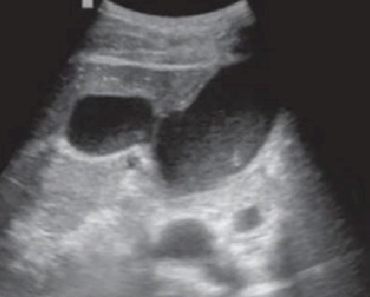

- 간문부와 직경이 큰 문맥관 주변에 호발 한다.

- portal vein을 따라 산재된 낭성병변 (포도송이 모양)

- 원인은 주로 간경변, 알코올성 간질환이 심한 환자에서 발견된다.

담관주변 낭종 (Peribiliary cyst) 췌담관 이상 유합 (Anomalous PancreaticoBiliary ductal Union , APBU)